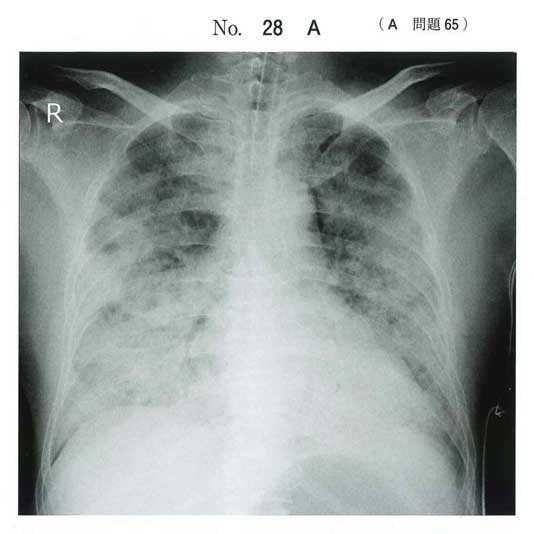

ARDSの問題とはこれですか。

ARDSというよりただの溺水では

海水溺水は浸透圧差から肺水腫をきたしやすいとされています